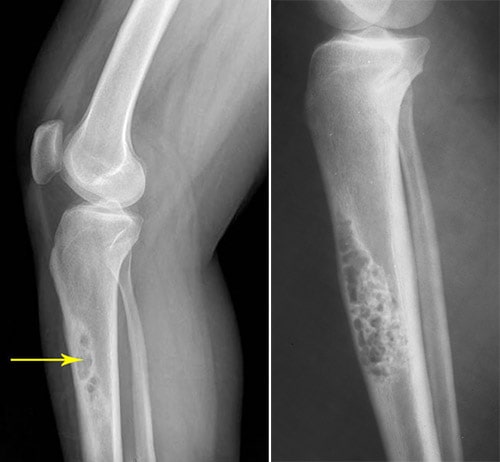

x-rays of OFD and adamantinoma

(Left) This x-ray of the tibia taken from the side shows several smaller areas of tumor, which is a sign of OFD. (Right) The typical "soap bubble" appearance of an adamantinoma is obvious in this tibia x-ray.